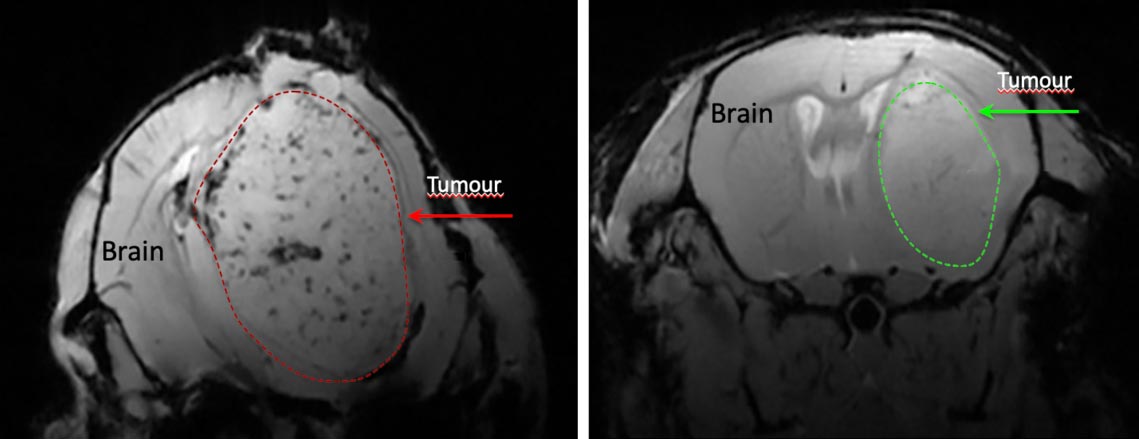

L’aggregazione di cellule tumorali nel glioblastoma senza trattamento, a sinistra, e come la niacina impedisce l’aggregazione cellulare. Credito: Per gentile concessione del laboratorio Yong.